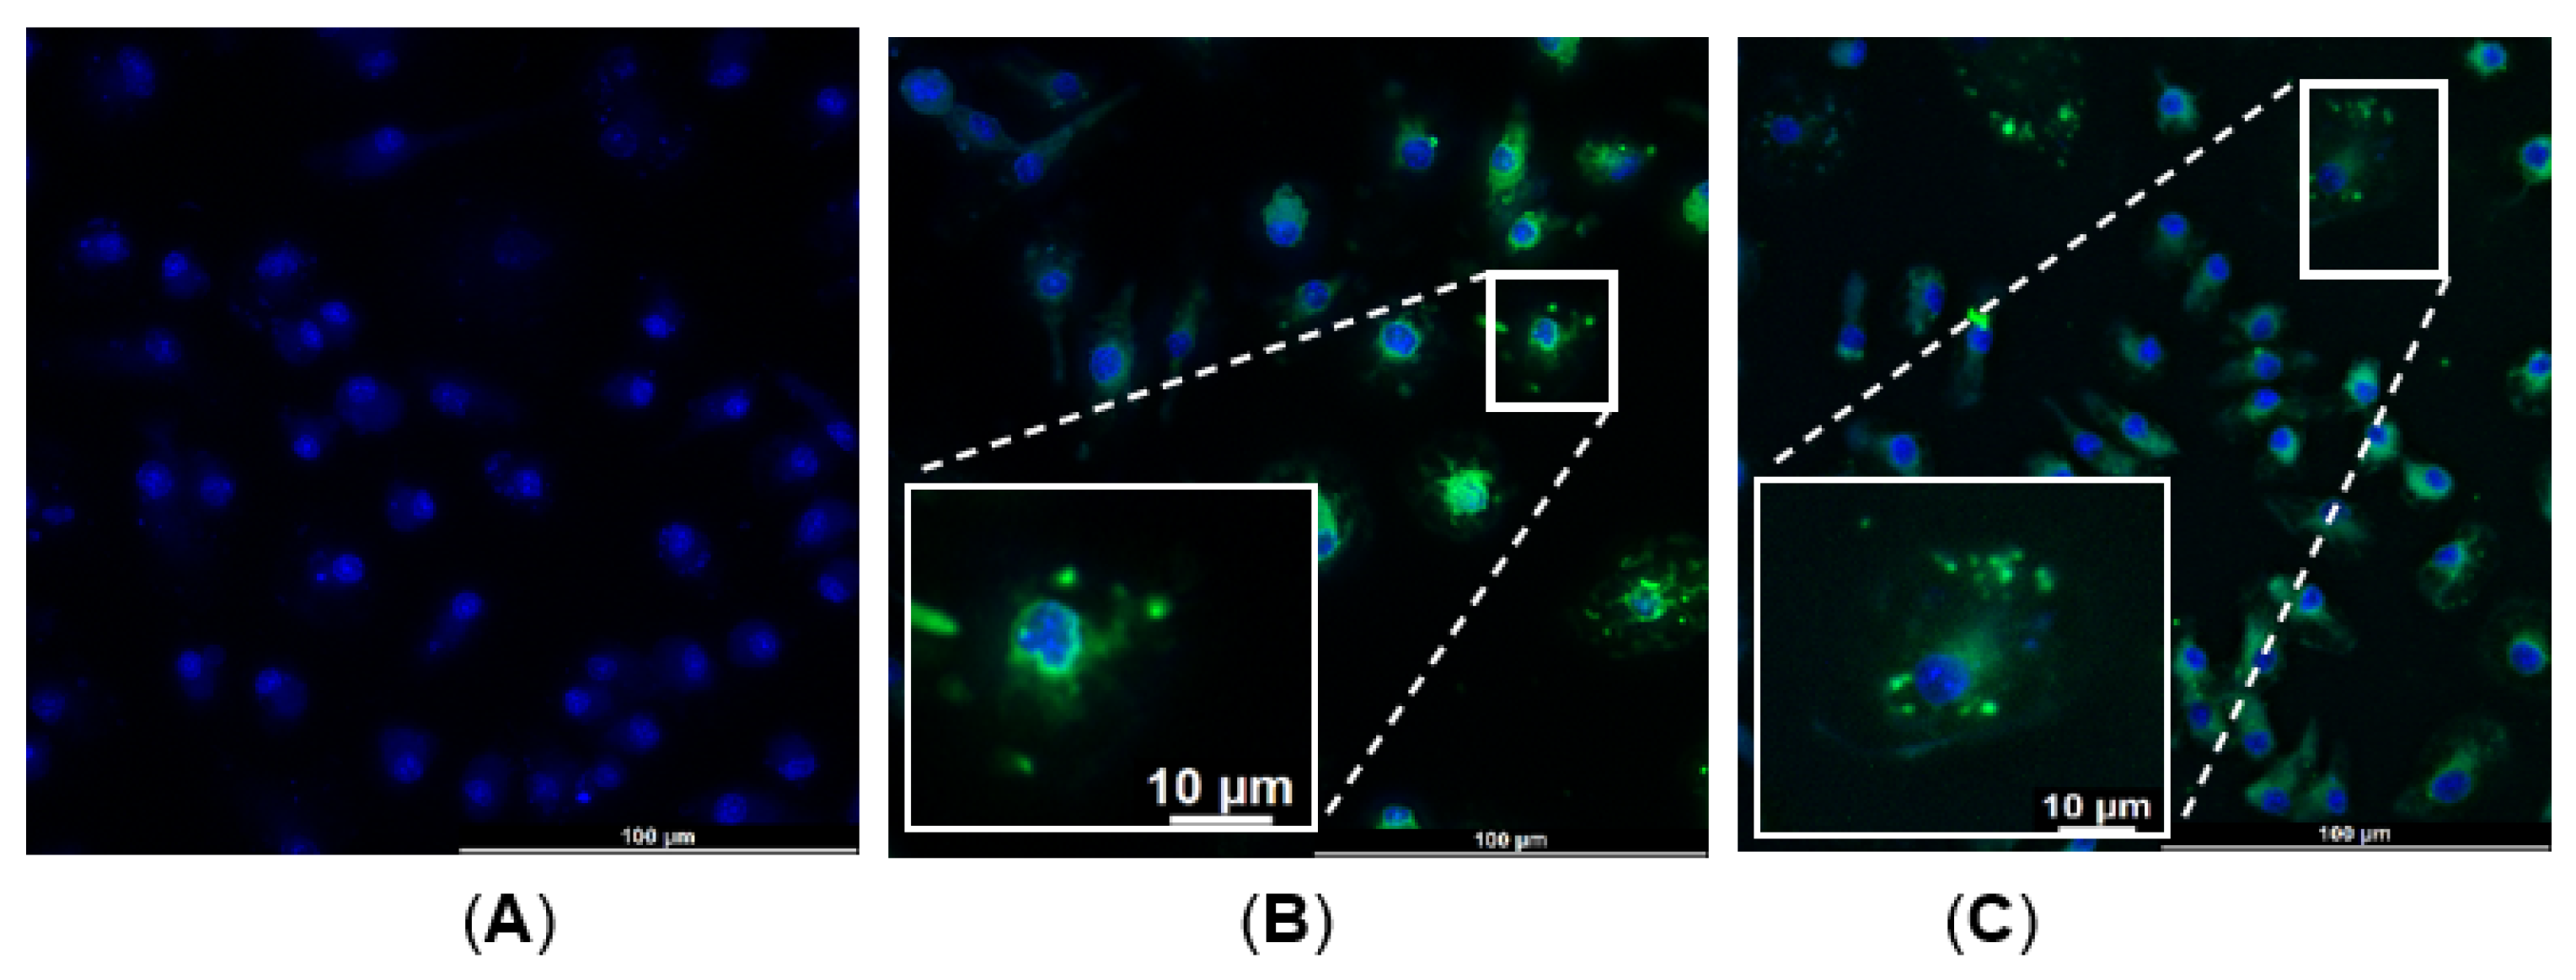

2.1.3. Bone-Marrow-Derived Macrophages (BMDM)—α-MSH-SM-Liposome Uptake Assay

4.4. Macrophage and α-MSH-SM-Liposomes Uptake Assay

4.4.1. Preparation of Bone-Marrow-Derived Macrophages In Vitro

4.4.2. BMDM Quality Check with Flow Cytometry

4.4.3. Liposome Assay with BMDM